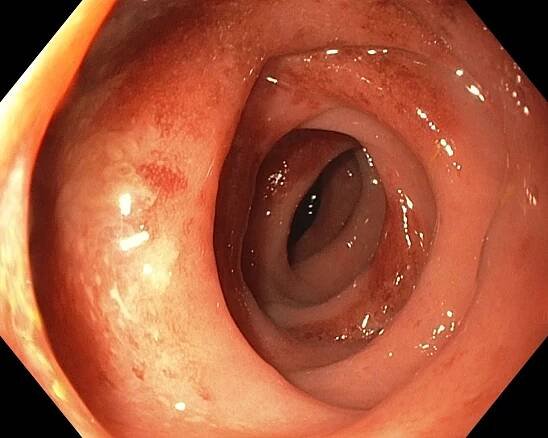

Segmental colitis associated with diverticulosis

Diverticulosis is the condition of having multiple pouches (diverticula) in the colon that are not inflamed. These are outpockets of the colonic mucosa and submucosa through weaknesses of muscle layers in the colon wall. [1 ] Diverticula do…